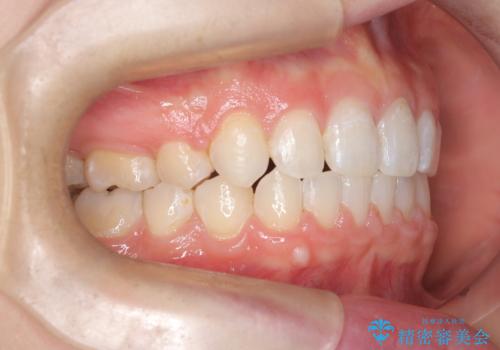

- 右上の八重歯と歯のデコボコ、そして上下の歯の中心(正中)のズレを気にされて来院されました。精密な検査の結果、歯が並ぶスペースが不足しているため、上顎の小臼歯(前から数えて4番目の歯)を抜歯し、そのスペースを利用して歯並び全体を整える治療計画を立案しました。これにより、八重歯の位置を適切に改善し、叢生(歯のデコボコ)を解消するとともに、上下の正中線のズレも改善することを目指します。

今回の矯正治療では、歯が並ぶスペースを確保するため、上顎の小臼歯を抜歯しました。抜歯によってできたスペースを有効活用し、ワイヤーやブラケットを使って右上の八重歯を適切な位置へ移動させ、叢生を解消していきました。また、治療を通じて上下の歯の中心である正中線のズレも改善するよう、慎重に歯を動かしました。治療の結果、長年気にされていた八重歯と歯のデコボコが解消され、上下の正中線も一致。機能的にも審美的にもバランスの取れた、美しい歯並びと笑顔を獲得していただけました。